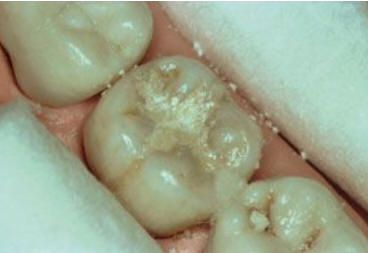

Una morfología de la fisura estrecha, con forma de botella de "Coca-Cola" genera un nicho ecológico ideal para la colonización de cualquier bacteria productora de ácidos. Al no poder remover en forma períodica dicho biofilm de una zona tan estrecha, el ataque ácido genera una lesión cariosa en la dentina, con un aspecto de esmalte intacto a la inspección visual, o sea un típico código 3 y 4 de ICDAS Completo. (Caries Moderada para el ICDAS COMBINADO)

Por este motivo es importante realizar el sellado de las fosas y fisuras de molares y premolares cuando comienza su erupción dentaria, como método de prevención eficaz de caries.

Código 3 (Caries moderada) in vitro. Los códigos 3 in vivo debe ser sellado para evitar el avance del proceso carioso. (MNO)

Código 4 (Caries moderada) in vitro. Los códigos 4 in vivo deben ser tratados en forma operatoria con preservación dental (MOPD), porque presentan dentina infectada.